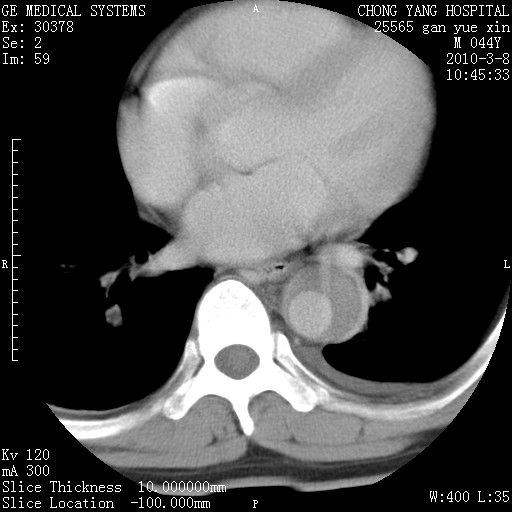

标题: CT24940:主动脉增强,典型病例。 [打印本页]

标题: CT24940:主动脉增强,典型病例。

夹层动脉瘤。

动脉夹层

夹层动脉瘤,典型

主动脉夹层。

动脉夹层的分型:

⒈debakey分型:根据主动脉夹层累及部位,分为三型:ⅰ型:原发破口位于升主动脉或主动脉弓部,夹层累及升主动脉、主动脉弓部、胸主动脉、腹主动脉大部或全部,少数可累及髂动脉。ⅱ型:原发破口位于升主动脉,夹层累及升主动脉,少数可累及部分主动脉弓。ⅲ型:原发破口位于左锁骨下动脉开口远端,根据夹层累及范围又分为ⅲa,ⅲb。ⅲa型:夹层累及胸主动脉。ⅲb型:夹层累及升主动脉、腹主动脉大部或全部。少数可累及髂动脉。

⒉stanford分型:a型:夹层累及升主动脉,无论远端范围如何。b型:夹层累及左锁骨下动脉开口以远的降主动脉。

夹层动脉瘤,少量胸水

夹层动脉瘤;左侧少量胸腔积液。

典型主动脉夹层。